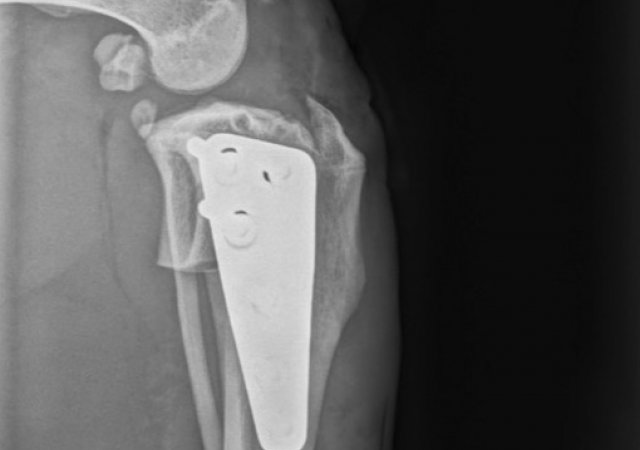

Patellaluxation

Nicht nur kleine Hunde wie Jack Russel Terrier, Yorkshire Terrier, Chihuahua und co. sind von der Patellaluxation (das Herausspringen der Kniescheibe) betroffen. Die Erkrankung findet sich bei Hunden aller Gewichtsklassen und bei einer Vielzahl an Rassen wie auch Mischlingen. Auch bei Katzen treten Probleme mit der Kniescheibe auf, wenn diese nicht dort sitzt, wo sie hingehört.

Nicht in allen Fällen bedarf es einer operativen Versorgung, jedoch sollte man die mittelfristigen Folgen einer ständig luxierenden Patella auf keinen Fall unterschätzen. Es besteht das erhöhte Risiko eines Kreuzbandrisses und kommt häufig zu Abnutzungen und einer dadurch bedingten Ausdünnung des Knorpels sowie zu Arthrosen.

Unter Berücksichtigung der individuellen Faktoren jedes Patienten (u.a. Alter, Gewicht und Aktivitätsgrad) entscheiden wir, welche Therapie zu Ihrem Tier passt.

Ist eine OP unausweichlich, so wird meist eine Transposition der Tuberositas Tibiae sowie eine Sulcoplastie durchgeführt. Bestehen zusätzlich massive Fehlstellungen der Hintergliedmaßen oder eine HD, können auch weitere Operationen wie Umstellungsosteotomien oder Operationen am Hüftgelenk erforderlich werden.